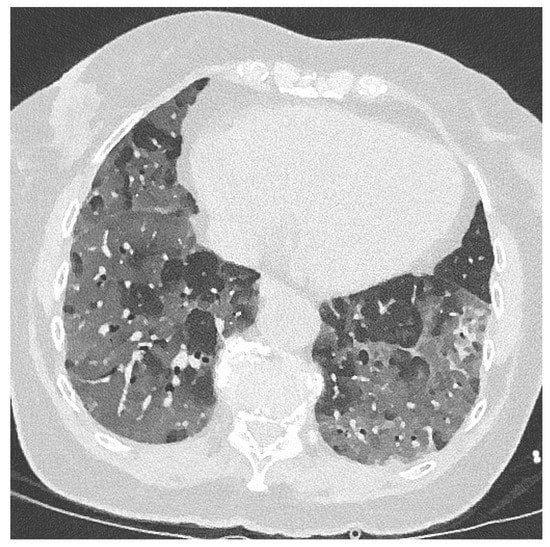

Azole-Resistant COVID-19-Associated Pulmonary Aspergillosis in an Immunocompetent Host: A Case Report

2. Case Report and Results